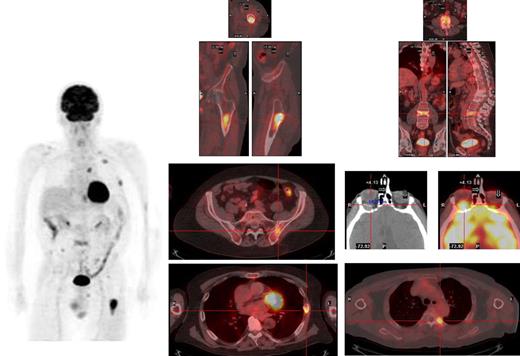

Sufficient (usually at least 5 mL) bone marrow (BM) should be obtained, not only for morphology but also for fluorescent in situ hybridization (FISH) analysis of key genetic events; this latter technique must be performed either in purified plasma cells or in combination with immunofluorescent detection of light chain restricted plasma cells (cIg-FISH) for t(4;14), t(14;16) and deletion of 17p, as these abnormalities identify high-risk disease.17 Metaphase cytogenetics should also be garnered when possible; the use of standard metaphase cytogenetics is often of low yield, but when positive for hypodiploidy, deletion of chromosome 13 or complex karyotype, with the exception of hyperdiploidy, imparts a particularly poor prognosis.18 Suggested genetic testing of patients is highlighted in Table 1. Finally, although the conventional skeletal survey remains the standard method for evaluation of bone lesions, magnetic resonance imaging (MRI) is more sensitive and is recommended to exclude spinal cord compression, soft tissue mass in a localized painful area or for assessing BM involvement in patients with solitary plasmacytoma and smoldering myeloma.19 The role of positron emission tomography-computed tomography (PET-CT) is less well defined in MM but can be useful for detecting extramedullary disease, unsuspected bone lesions, and evaluating patients with plasmacytoma as well as nonsecretory or oligosecretory MM.20-22 We have in our early experience found PET-CT to be of significant interest in many patients, providing reassurance when negative in smoldering disease and often revealing a previously unappreciated extent of disease in higher-risk patients (Figure 1).

Myeloma deposits are identified by PET-CT in a relapsing patient in the left femur, ribs, thoracic and lumbar spine, and left iliac crest, and a previously unsuspected extramedullary lesion is identified behind the left orbit.